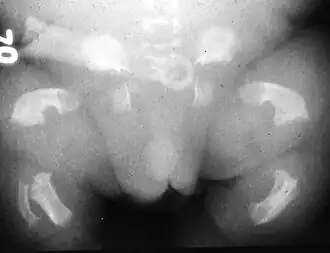

Le nanisme thanatophore est le plus fréquent des nanismes létaux. Ce nanisme a une traduction échographique précoce permettant souvent le diagnostic anténatal.

Description clinique

Il existe deux types de nanisme thanatophore.

- Raccourcissement très important des fémurs et des humérus

- Thorax très étroit

- Longueur du tronc normale

- Grosse tête ou macrocéphalie

- Excès de liquide amniotique ou hydramnios